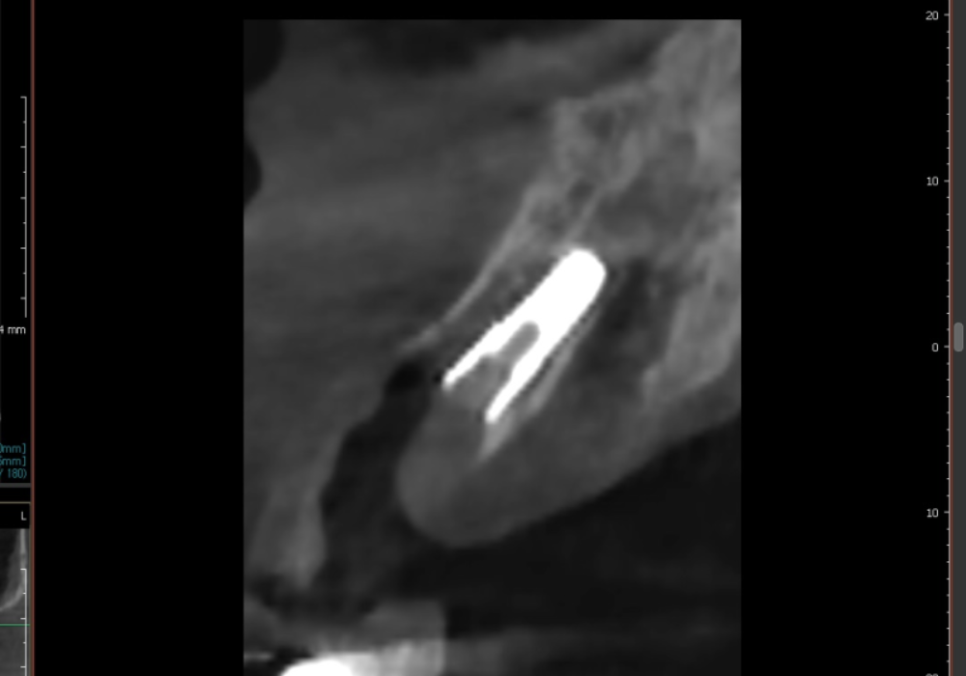

더 자세히 살펴보기 위해

CT를 확인해 보았습니다.

CT 상에서 검게 투과되어 보이는 부분들이

모두 염증인데,

이미 치아를 지탱할 잇몸뼈가 상당 부분

녹아 없어진 상태네요..

특히 입천장 쪽 잇몸뼈가 소실되면서

치아를 받쳐주는 '지지대'가

아예 사라진 상황이었는데요,

결국 뿌리가 뼈에 간신히 걸쳐 있다 보니,,

치아는 앞쪽으로 뻗치면서

힘없이 아래로 내려앉을 수밖에 없겠죠.